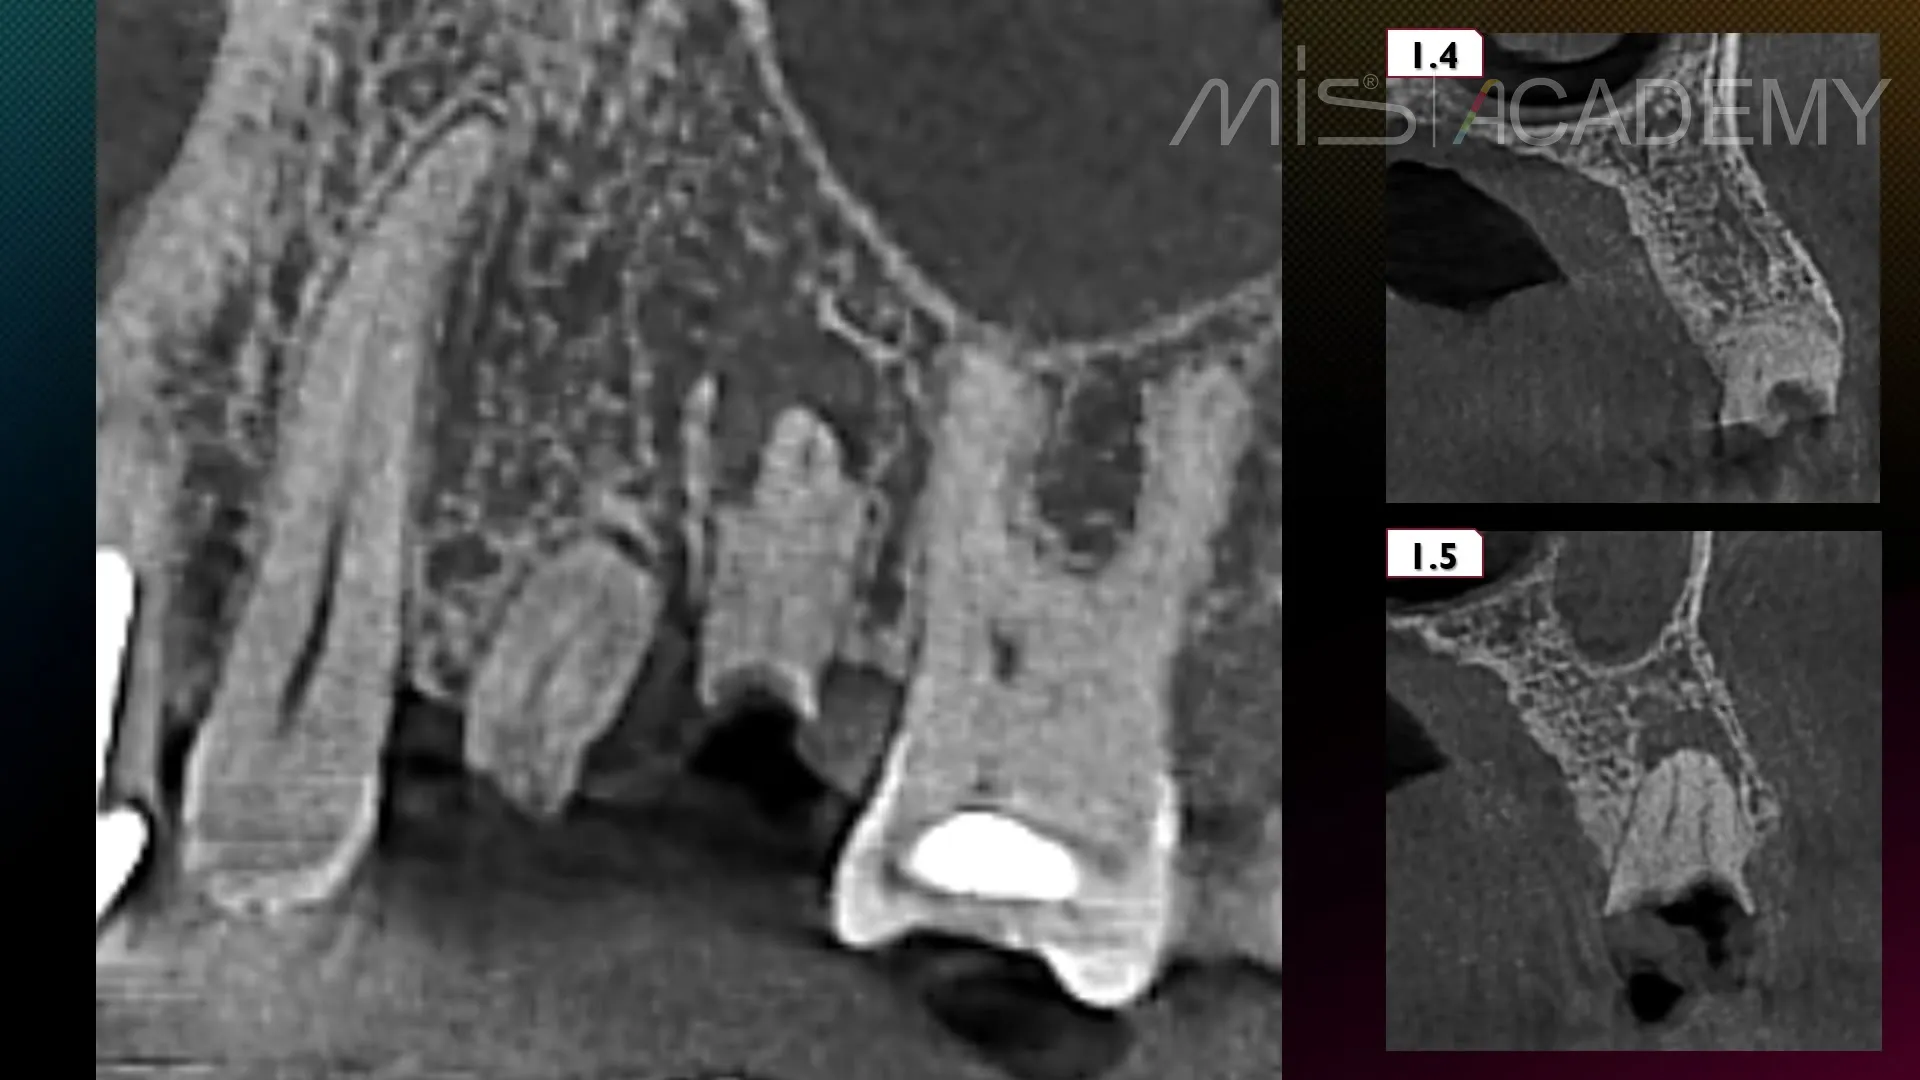

— Удаление корней 2.4, 2.5.

— Установка имплантатов MIS C1.